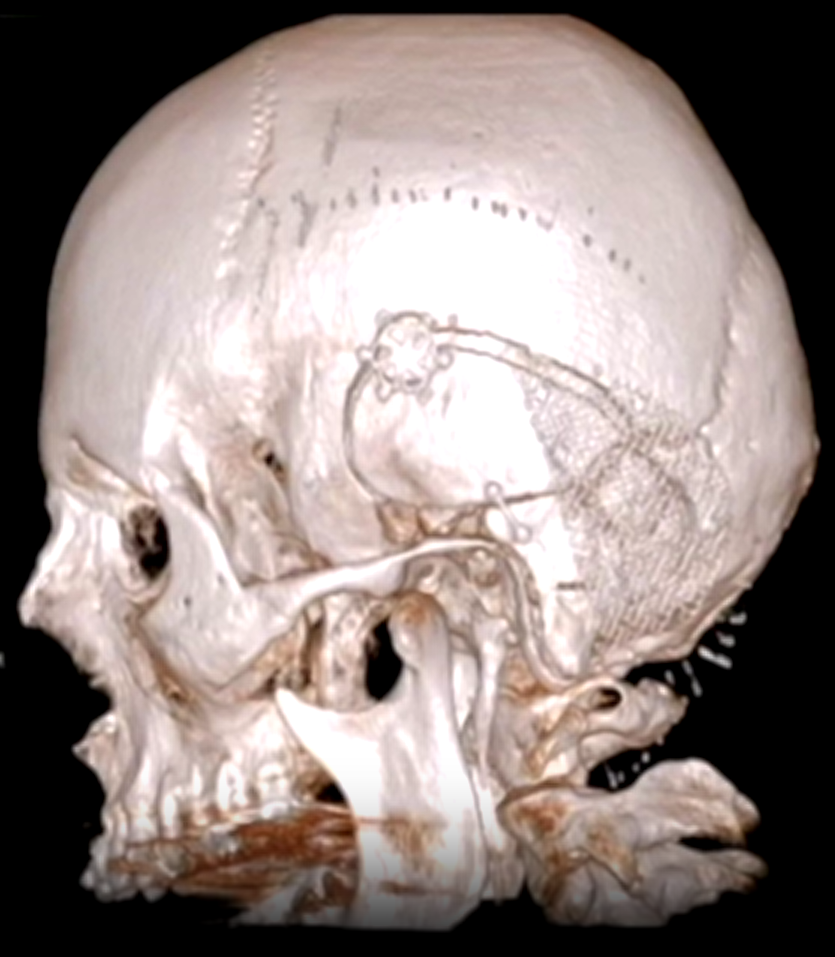

第三步是联合岩骨入路:这是福洛里希教授的核心手术策略——将岩前入路与岩后入路联合实施,同时配合颞顶枕开颅,从多角度多方向逼近肿瘤。这一入路方式的最大优势在于,能够在相对短的手术距离内为岩斜区提供宽阔的操作视野,同时将对脑组织的牵拉损伤降至最低。福洛里希教授曾于2019年在《Acta Neurochirurgica》杂志发表专题论文,系统详解了这一入路的每个关键操作步骤——这已不仅仅是一台手术方案,而是一套经过系统论证与长期实践检验的颅底手术理念体系。

最扣人心弦的,是肿瘤与脑干之间的精细解剖过程。基底动脉的穿支血管,直径不足一毫米,却直接关系到脑干的血液供应。福洛里希教授在高倍显微镜下,以镊子逐层分离蛛网膜界面,以CUSA超声吸引刀分次减瘤,以显微剪刀逐一切断肿瘤与血管之间每一根细微的蛛网膜桥接结构——操作的精细程度,不亚于在千钧一发中完成绣花。动眼神经、外展神经,在肿瘤包裹之中被逐一辨认、分离、完整保护。颅底重建阶段,以腹部脂肪填塞术腔,硬脑膜水密缝合,骨瓣经微型钢板精准复位。